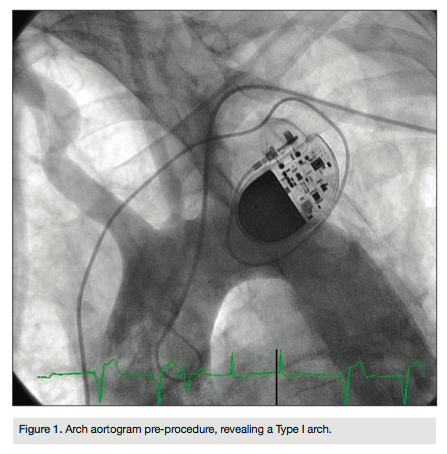

arch aortogram revealed a Type I aortic arch with no significant atheroma (Figure 1). A Simmons 2 catheter (AngioDynamics) was used to selectively engage the right common carotid artery by looping the catheter in the right coronary cusp. A stiff-angled Glidewire (Terumo) was then used as an anchor in the right external carotid artery (Figure 2A) and a Pinnacle Destination sheath (Terumo) advanced into the right common carotid artery (Figure 2B). Selective angiogram confirmed an 80% stenosis of the right internal carotid artery (Figure 3). An Emboshield distal embolic protection device (Abbott Vascular) was deployed in a straight segment in the distal right internal carotid artery. After pre-dilation with a Viatrac 4.0 x 20 mm

balloon (Abbott Vascular), an Xact 6-8 x 30 mm self-expanding stent (Abbott Vascular) was deployed in the right internal carotid artery, and post-dilated using a Viatrac 5.0 x 20 mm balloon. Final angiogram confirmed excellent angiographic result and brisk flow (Figure 4). The patient was discharged home the following day after initiation of dual antiplatelet therapy indefinitely.